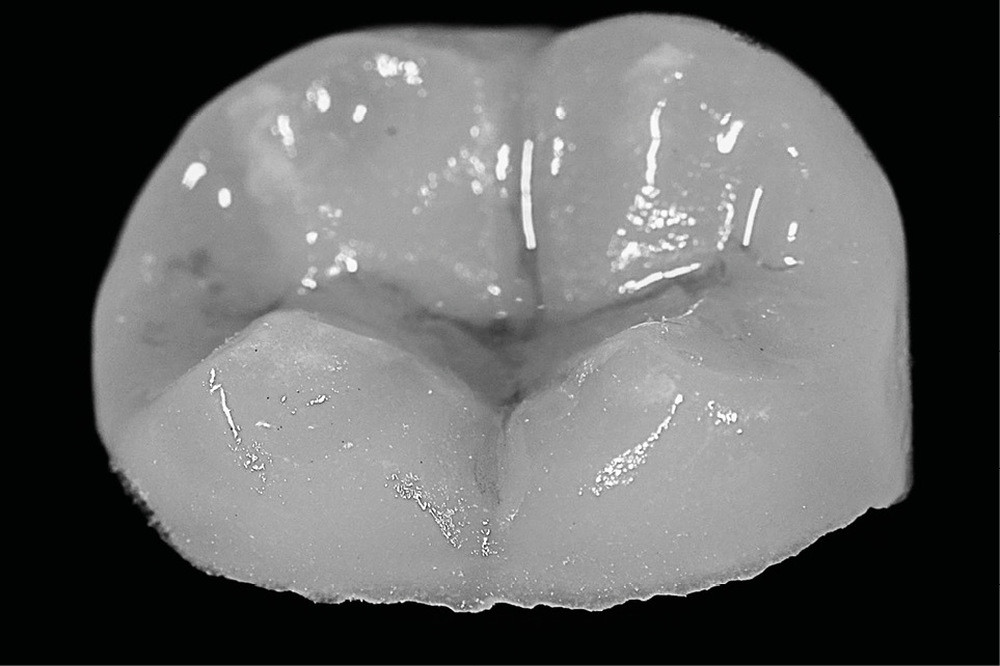

La procédure clinique est construite en deux séances. Lors de la première séance, d’une durée de 3 h, nous effectuons l’endodontie, la base intermédiaire, la préparation de l’overlay, et l’empreinte optique. La cavité d’accès réalisée est aussi petite que possible, mais aussi large que nécessaire afin de favoriser un maximum de préservation tissulaire tout en permettant un accès raisonnable aux canaux (fig. 2).

Une partie de la crête marginale distale est éliminée pour traiter la fissure. Une reconstruction pré-endodontique définitive est préférable à ce stade, afin de maximiser les valeurs d’adhérence du composite en évitant les contaminants endodontiques (fig. 3).